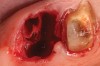

Figure 12  A patient who had tooth No. 2 extracted using Piezosurgery, periotomes, thin-bladed elevators, and small-beaked forceps, enabling preservation of all bony peaks.

Figure 12

Figure 13  After debridement of the socket, a mixture of pure-phase β-TCP and heme from the surgical site was covered with a dense polytetrafluoroethylene (PTFE) barrier.

Figure 13

Figure 14  At the time of the 6-month reentry, the site appeared healed. Full ridge height preservation and graft resorption with bony replacement were confirmed radiographically.

Figure 14